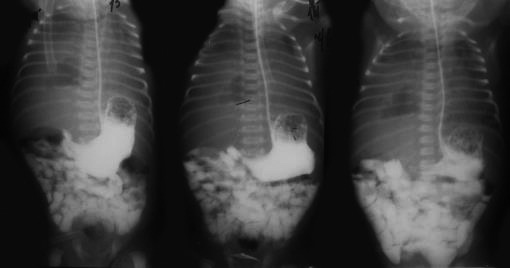

Рис. 5. Рентгеноконтрастное исследование с пассажем контраста для исключения правосторонней диафрагмальной грыжи. Снимки на 10 мин, 30 мин, 1 ч. Контрастирования тени правой половины грудной клетки нет.

В связи с сохраняющейся дыхательной недостаточностью ребенку проведено МСКТ грудной клетки (29.09), заключение: картина дополнительного образования правой половины грудной клетки, дифференцировать с правосторонней диафрагмальной грыжей. По данным МРТ органов грудной клетки (02.10) заключение: картина миграции правой и левой доли печени и петли кишечника в правую плевральную полость, ателектаз нижней доли правого легкого, застойные явления нижней доли левого легкого, купол диафрагмы визуализировать не удалось. Ребенок прооперирован 12.10 – срединная лапаротомия, пластика дефекта правого купола диафрагмы (щель Бохдалека) местными тканями. Во время операции отмечалось интимное сращение висцеральной плевры нижней доли правого легкого к диафрагмальной поверхности печени, что расценено как последствия воспалительного процесса в легком и плевральной полости вследствие перенесенной пневмонии и давности процесса. Послеоперационный период протекал без осложнений, ребенок экстубирован (22.10), выписан домой в удовлетворительном состоянии (10.11).

Таким образом, напряженный правосторонний пневмоторакс вызвал перемещение печени и кишечника на место их физиологической локализации, что затруднило диагностику. В ряде случаев рентгенография с проходящим контрастом может оказаться неэффективной для распознавания петли кишки в грудной полости, поэтому методом выбора нужно считать МСКТ грудной клетки.